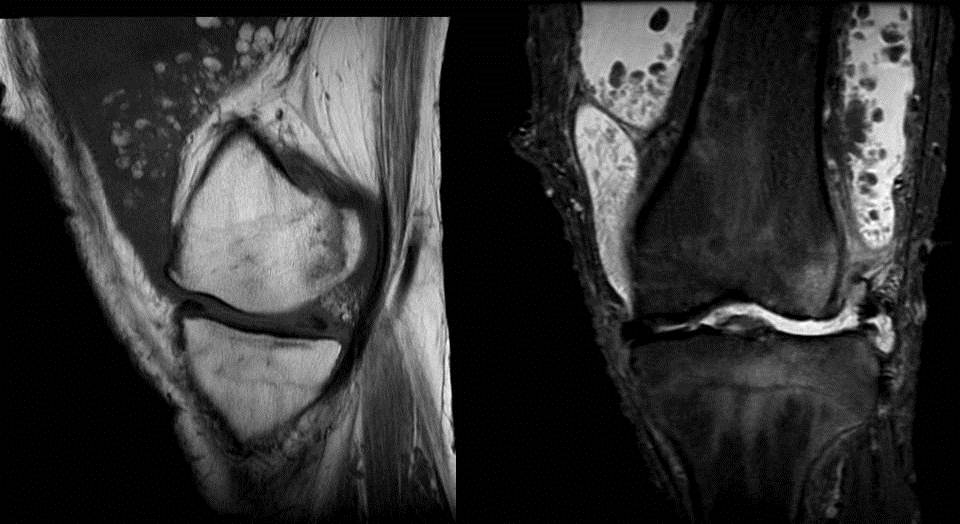

RADIODIAGNOSIS IMAGE COLLECTION Lipoma arborescens

From rakheeradimages.blogspot.com

RADIODIAGNOSIS IMAGE COLLECTION Lipoma arborescens Synovial Thickening Elbow Mri Synovial chondromatosis, pvns and rice bodies. mri reveals prominent diffuse villous or nodular proliferation of synovium and associated joint effusion. In a subgroup of patients, plicae, when thickened, may. Mri findings of synovial diseases. mri and ct or mr arthrography are useful tools in the diagnosis of elbow synovial fold. the differential diagnosis for the low intensity. Synovial Thickening Elbow Mri.